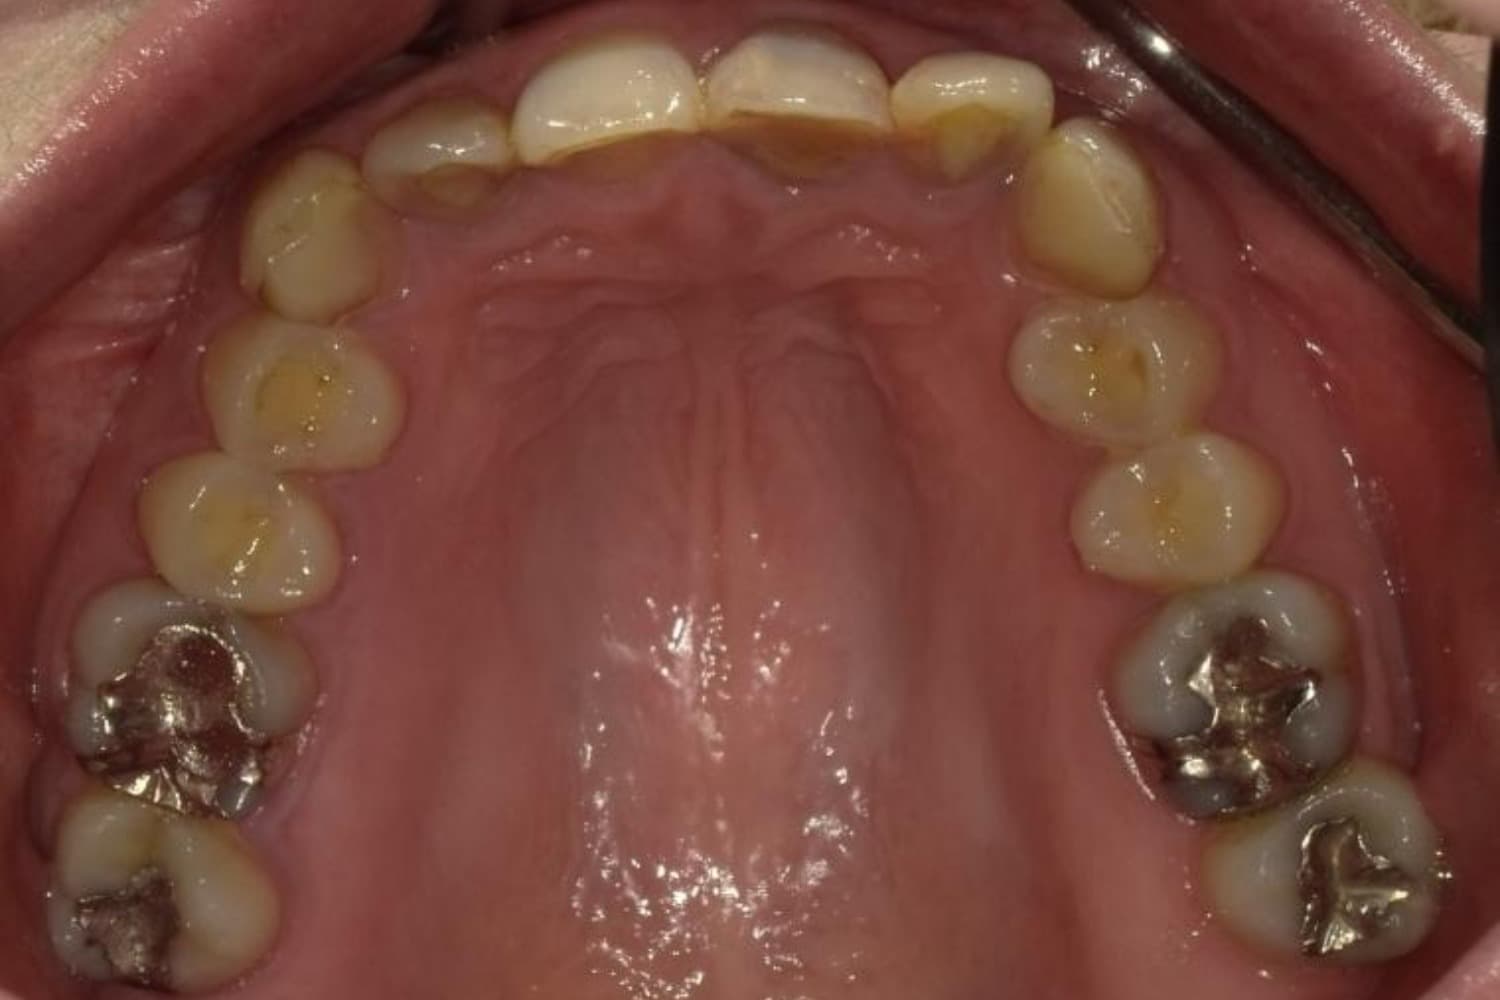

上顎前歯1本欠損症例(1)

Before

After

歯の根が割れていたため抜歯をおこないました。インプラント・ブリッジ・義歯それぞれのメリットやデメリットをお話させていただき、インプラントでの治療を選択されました。

年齢

46歳

性別

女性

主訴

前歯の色味が気になる

治療期間

11ヵ月

費用

60万円

副作用・リスク

インプラント治療は外科的な処置を伴い、多少の腫れや痛みが出ることがあります。 多くの場合は鎮痛薬で和らげることができます。